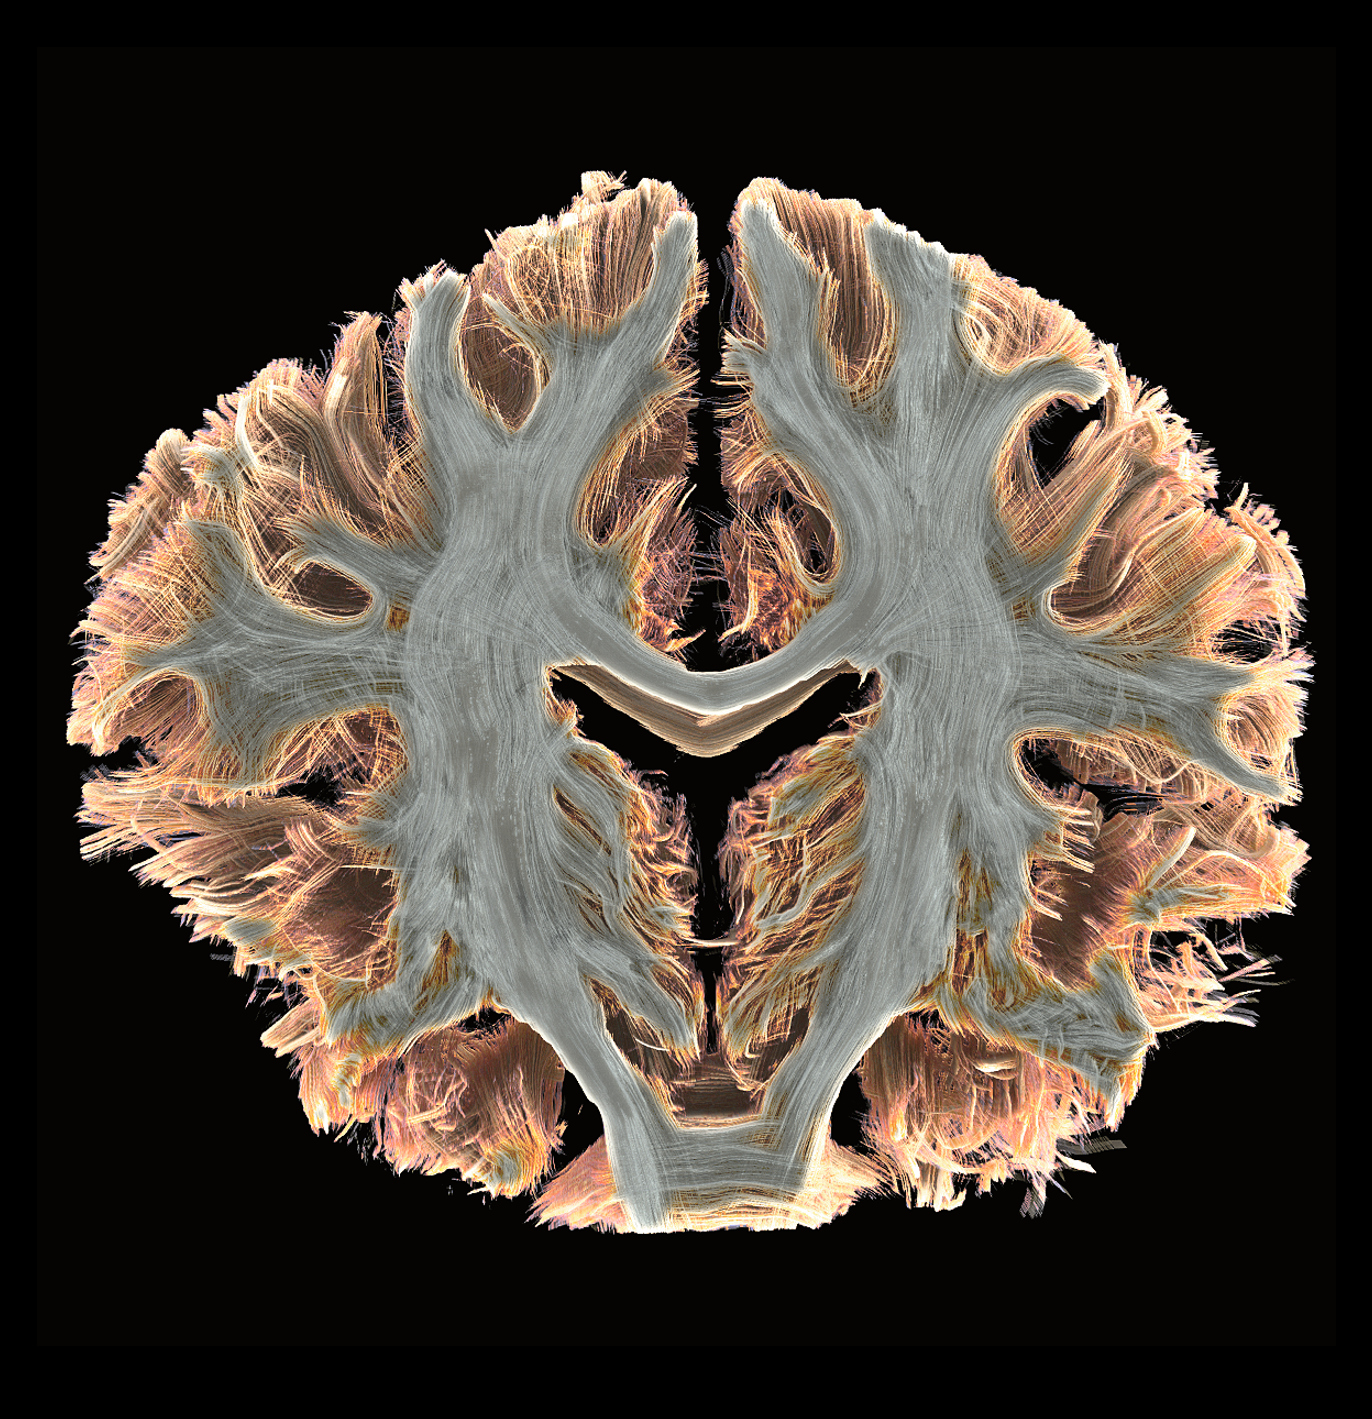

With a remarkable gradient strength of 130 mT/m and a slew rate of 250 T/m/s, the MAGNETOM Terra.X takes imaging precision to unprecedented levels compared to conventional systems equipped with 80 mT/m gradients. This enhanced gradient strength facilitates faster and more detailed imaging, allowing us to push the boundaries of what is possible in research and clinical diagnostics. A huge boost for functional, diffusion and structural MRI capabilities.

Revolutionary Ultra IQ Technology and Deep Resolve

The Siemens Healthineers MAGNETOM Terra.X is equipped with Ultra IQ Technology, including dynamic pTx, unlocking the full potential of 7T MRI. This revolutionary technology, coupled with Deep Resolve, leads to previously unheard resolution and acquisition speed. Researchers at Campus Biotech can now delve deeper into the intricacies of biological structures, paving the way for groundbreaking discoveries and advancements in medical knowledge.